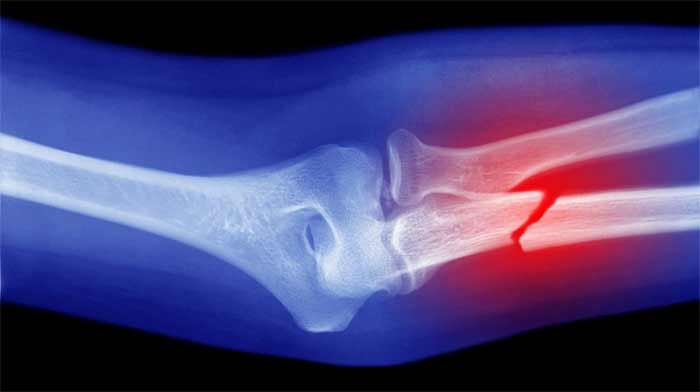

شکستگی استخوان چیه و چرا باید حواسمون بهش باشه؟

بیا ساده شروع کنیم. وقتی استخونت میشکنه، بدن تو مثل یه کارخونهی فوق پیشرفته شروع میکنه به تعمیر خودش. اول یه التهاب کوچولو اطراف محل شکستگی ایجاد میشه، بعد سلولهای خاص میان و یه بافت نرم (مثل یه چسب موقت) درست میکنن. کمکم این بافت نرم سفت میشه و به استخون جدید تبدیل میشه. اما این پروسه مثل پختن یه کیک خوشمزه زمانبره و نیاز به مواد اولیهی درست داره.

حالا اگه مواد اولیهی نامناسب (مثل غذاهای مضر) به بدن بدی یا کارخونه رو با عادتهای بد بههم بریزی، جوشخوردن استخون کند میشه یا حتی بدتر، ممکنه درست جوش نخوره! برای همین، تغذیه تو این دوره مثل یه سوپرمن عمل میکنه و میتونه سرعت و کیفیت ترمیم رو حسابی بالا ببره.